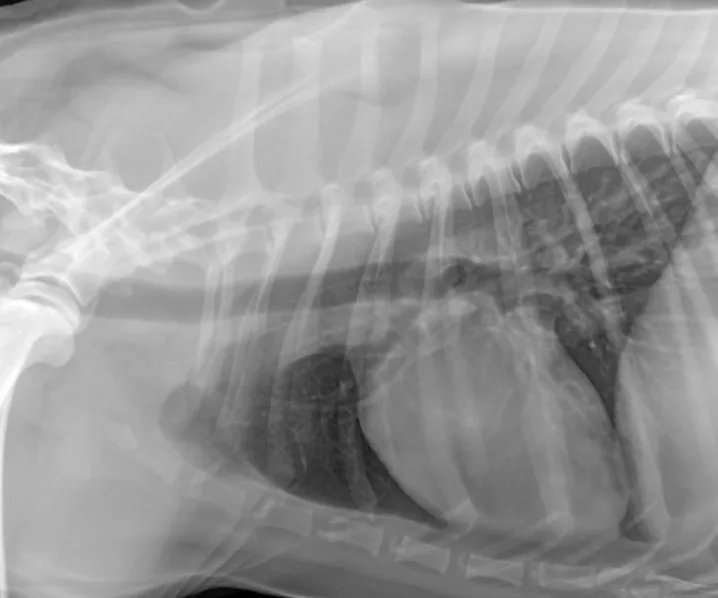

An alveolar pattern in the entire left hemithorax and in the hilar and midzone regions of the right caudal lung lobe. Multiple air bronchograms are observed in the left hemithorax on both views.

Recheck thoracic radiographs obtained 35 hours after admission revealed a progressive alveolar pattern affecting the left cranial, left caudal, and right caudal lung lobes. Consolidation was noted in the left cranial lung lobe (Figure 1, above).